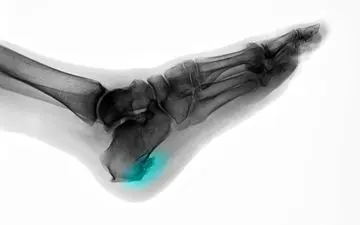

خار پاشنه یکی از شایعترین دلایل درد در ناحیه پاشنه پا است که میتواند فعالیتهای روزمره را بهشدت تحت تأثیر قرار دهد.

یکی از شایعترین علل درد پاشنه پا بوده که با درد و تورم رباط کف پا ( رباطی که استخوان پاشنه را به انگشتان وصل میکند )…